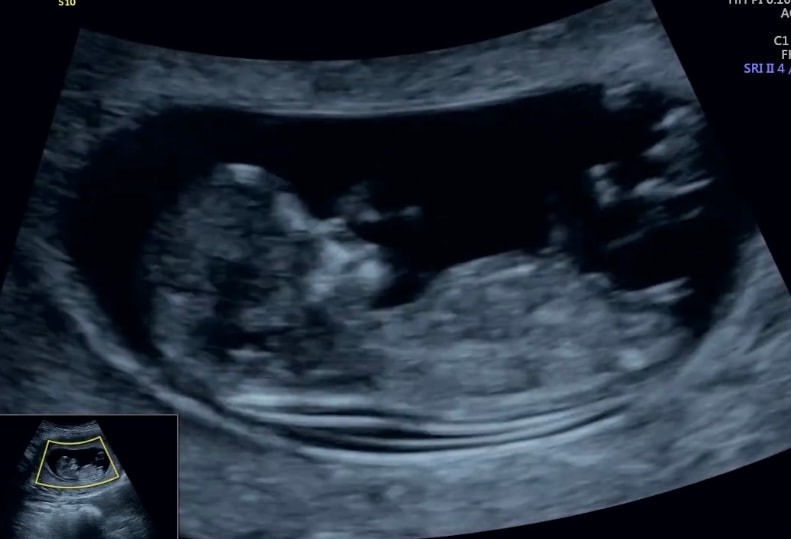

Алина, Изображениедоча в 12 недель.

Алина, мне было видно её без бугорка. Вот эта утонченнтсть, Вам не видно? 😅

Анюта Денисова, нееет, у меня круглый бутуз, там утонченности нет😄 она была в 11.4, а через неделю как ветром сдуло Изображение

Алина, 3Д так себе Изображение